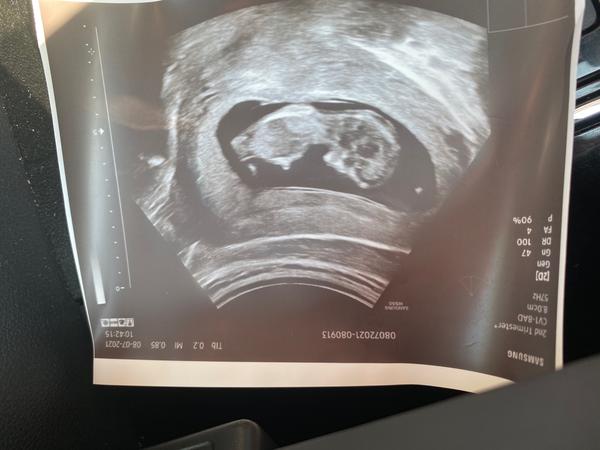

Ahoj holky,do diskuze se přidávám poprvé,ale když vidim vaši debatu,nedá mi to,vás nepoprosit o názor😀čekáme druhé mimčo,od začátku doktor tvrdil holku,kterou potvrdili na 100% na genetice ve 21 tt a najednou ve 30 si doktor není jisgý,zda neviděl chlapečka,dostala jsem i fotku a já myslim,že to je spíš 100% chlapeček😀na pohlaví nám nezáleží,ale samozřejmě mě všichni zásobily růžovou,tak teď jsem na vážkách,zda se toho rovnou zbavit,nebo počkat,naštěstí neitrální věci máme po prvním chlapečkovi😀

@marta6793 tak uvidíte, máte ještě nějaký ultrazvuk ? A fotku z 1. nebo z 2. scr. nemáte, kde by šlo vidět pohlaví ? Také máme potvrzenou holčičku (ve 22.tt), MUDr nám to napsala i do zprávy, už spoustu nakoupených věci tak doufám, že to tak zůstane. Ve 12.tt (genetika) - holka, v 15.tt- jiná MUDr spíše kluk ale koukla jen tak rychle ze spodu, ve 22.tt (genetika) ta samá MUDr z 1.scr. viděla pysky...docela dlouho to kontrolovala a říkala že už z toho kluk nebude.

@kotate no tak snad vám to tak zůstane😊nene nic jiného nemáme,na té gebetice to řekla doktorka hned,ani jsem se nestihla podívat,já od začátku byla přesvědčená,že to bude kluk,tak jsem se jen zaraženě ze srandy zeptala,jestli fakt máme kupovat růžovou a ona,že je to jasné a že určitě😃no a pak vlastně na tom 3d špekulovala doktorka jestli nezahlídla kulky a vracela se tam snad 10x a pak řekla,že je to určitě holka,že mají to pohpaví oteklé a že ji to zmátlo,tak uvidíme asi až opravdu u porodu😀